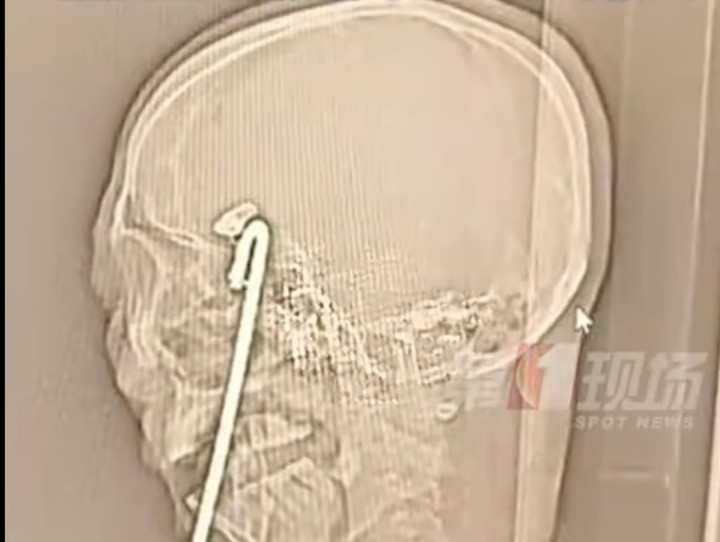

Hình ảnh X-quang cho thấy, phần đầu của thanh sắt dài 40cm chỉ cách các mạch máu chính của não 2mm. Một thách thức lớn nữa là phần đầu này được gắn bằng một cái kẹp, rất khó để tháo thanh sắt ra mà không làm tổn thương não, mắt hoặc miệng.

Phim X-quang cho thấy thanh sắt gần chạm vùng não quan trọng của Aqiang. (Ảnh: QQ.com)